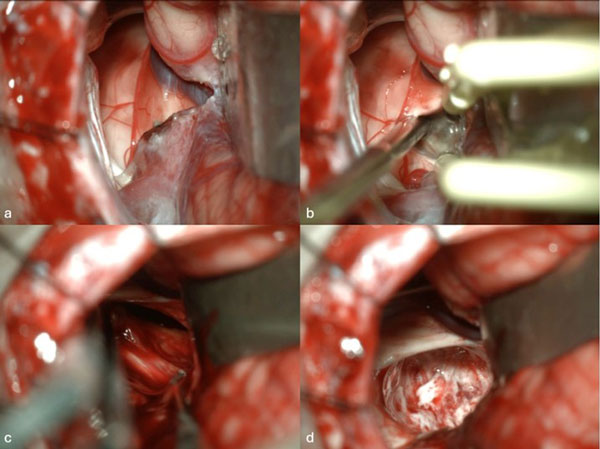

Caso 2: cavernoma pontino

Una paciente femenina de 28 años, sin antecedentes de sangrado previo, debutó con cefalea, náuseas y vómitos, asociado a diplopía secundaria a una parálisis del VI par derecho. La RM de encéfalo evidenció una malformación cavernomatosa centrada en puente y el pedúnculo cerebeloso medio derecho (Figura 3). Un mes después del sangrado, se realizó una exéresis de la lesión mediante un abordaje retrosigmoideo ampliado a través del pedúnculo cerebeloso medio (Figura 4), logrando una exéresis completa (Figura 5). Tras el procedimiento, la paciente evolucionó con hemihipoestesia del hemicuerpo izquierdo, sin otros síntomas agregados.

Figura 3. RM preoperatoria de encéfalo. Se evidencia una lesión única intraaxial centrada en puente y pedúnculo cerebeloso derecho, sugerente de un cavernoma roto. A, B y C) Imágenes ponderadas en T2 en cortes sagital, axial y coronal, respectivamente, donde se observa un importante hiperintensidad perilesional, sugerente de edema.

Figura 4. Imágenes intraoperatorias bajo microscopía. Abordaje retrosigmoideo ampliado a derecha, con ruta de ingreso transpedúnculo cerebeloso medio. A yB) Corticotomía en pedúnculo cerebeloso medio. C) Identificación y resección en bloque de la malformación cavernomatosa. D) Revisión del lecho, sin remanente.

Figura 5. RM postquirúrgica de encéfalo. Se evidencia una exéresis completa con hiperintensidad en T2 en regresión. A, B y C) Imágenes ponderadas en T2 en cortes coronal, axial y sagital, respectivamente.